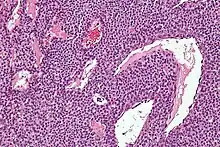

| Micrograph of a glomus tumor. H&E stain. | |

Histologically, glomus tumors are made up of an afferent arteriole, anastomotic vessel, and collecting venule. Glomus tumors are modified smooth muscle cells that control the thermoregulatory function of dermal glomus bodies. As stated above, these lesions should not be confused with paragangliomas, which were formerly also called glomus tumors in now-antiquated clinical usage. Glomus tumors do not arise from glomus cells, but paragangliomas do.

By histopathology, glomus tumors can be termed as follows:[7]

- Solid glomus tumor (75% of cases): Consisting predominantly of glomus cells, with poor vasculature and rare smooth muscle cells.

- Glomangioma (20% of cases): Tumors with a prominent vascular component.

- Glomangiomyoma (5% of cases): Tumors with prominent vascular and smooth muscle components.